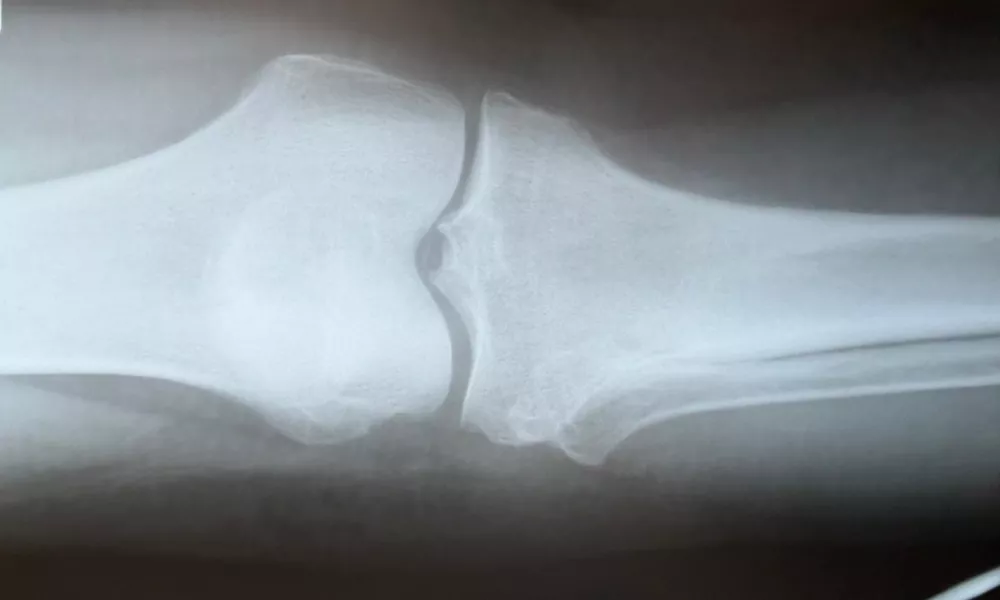

Хирурги Владимирского Областного центра спецмедпомощи провели сложную операцию по удалению крупной доброкачественной опухоли из сустава в колене у 70-летней пациентки. Образование, по диаметру сравнимое с куриным яйцом, причиняло женщине сильные болезненные ощущения.

Как рассказали в пресс-службе медучреждения, пациентка обратилась к специалистам с жалобами на интенсивную боль в колене при движении ноги и мучительные «простреливающие» ночью, из-за которых было невозможно спать. После осмотра и необходимых обследований было принято решение о хирургическом вмешательстве.

Осложняла ситуацию непосредственная близость малоберцового нерва, отвечающего за чувствительность и движение голени и стопы. Любое неверное движение могло привести к его повреждению и нарушению функций конечности.

«Операция потребовала применения микрохирургической техники. Нерв был аккуратно выделен и защищен, после чего опухоль удалось полностью удалить», - рассказали в Центре.